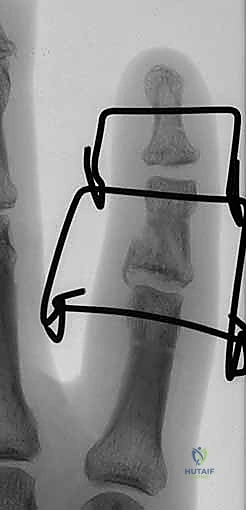

5. تجميع الإطار الديناميكي (Frame Assembly)

يقوم الدكتور هطيف بثني الأسلاك المعدنية بمهارة هندسية لتشكيل الإطار الخارجي. هناك عدة أنواع من الإطارات (مثل Suzuki Frame أو Compass Hinge). يتم توصيل الأسلاك ببعضها باستخدام أربطة مطاطية معقمة (Rubber Bands) أو نوابض طبية. هذه المطاطات تولد قوة شد مستمرة تسحب المفصل وتمنع احتكاك العظام المكسورة ببعضها.

6. الاختبار داخل غرفة العمليات

لا تنتهي العملية بمجرد تركيب الإطار. يقوم الدكتور هطيف بثني وفرد إصبع المريض تحت جهاز الأشعة للتأكد من أمرين:

* المفصل يتحرك بسلاسة دون أي إعاقة.

* السطح المفصلي يبقى في مكانه الصحيح (Concentric Reduction) طوال القوس الحركي، ولا يحدث أي خلع أو احتكاك للقطع المكسورة.